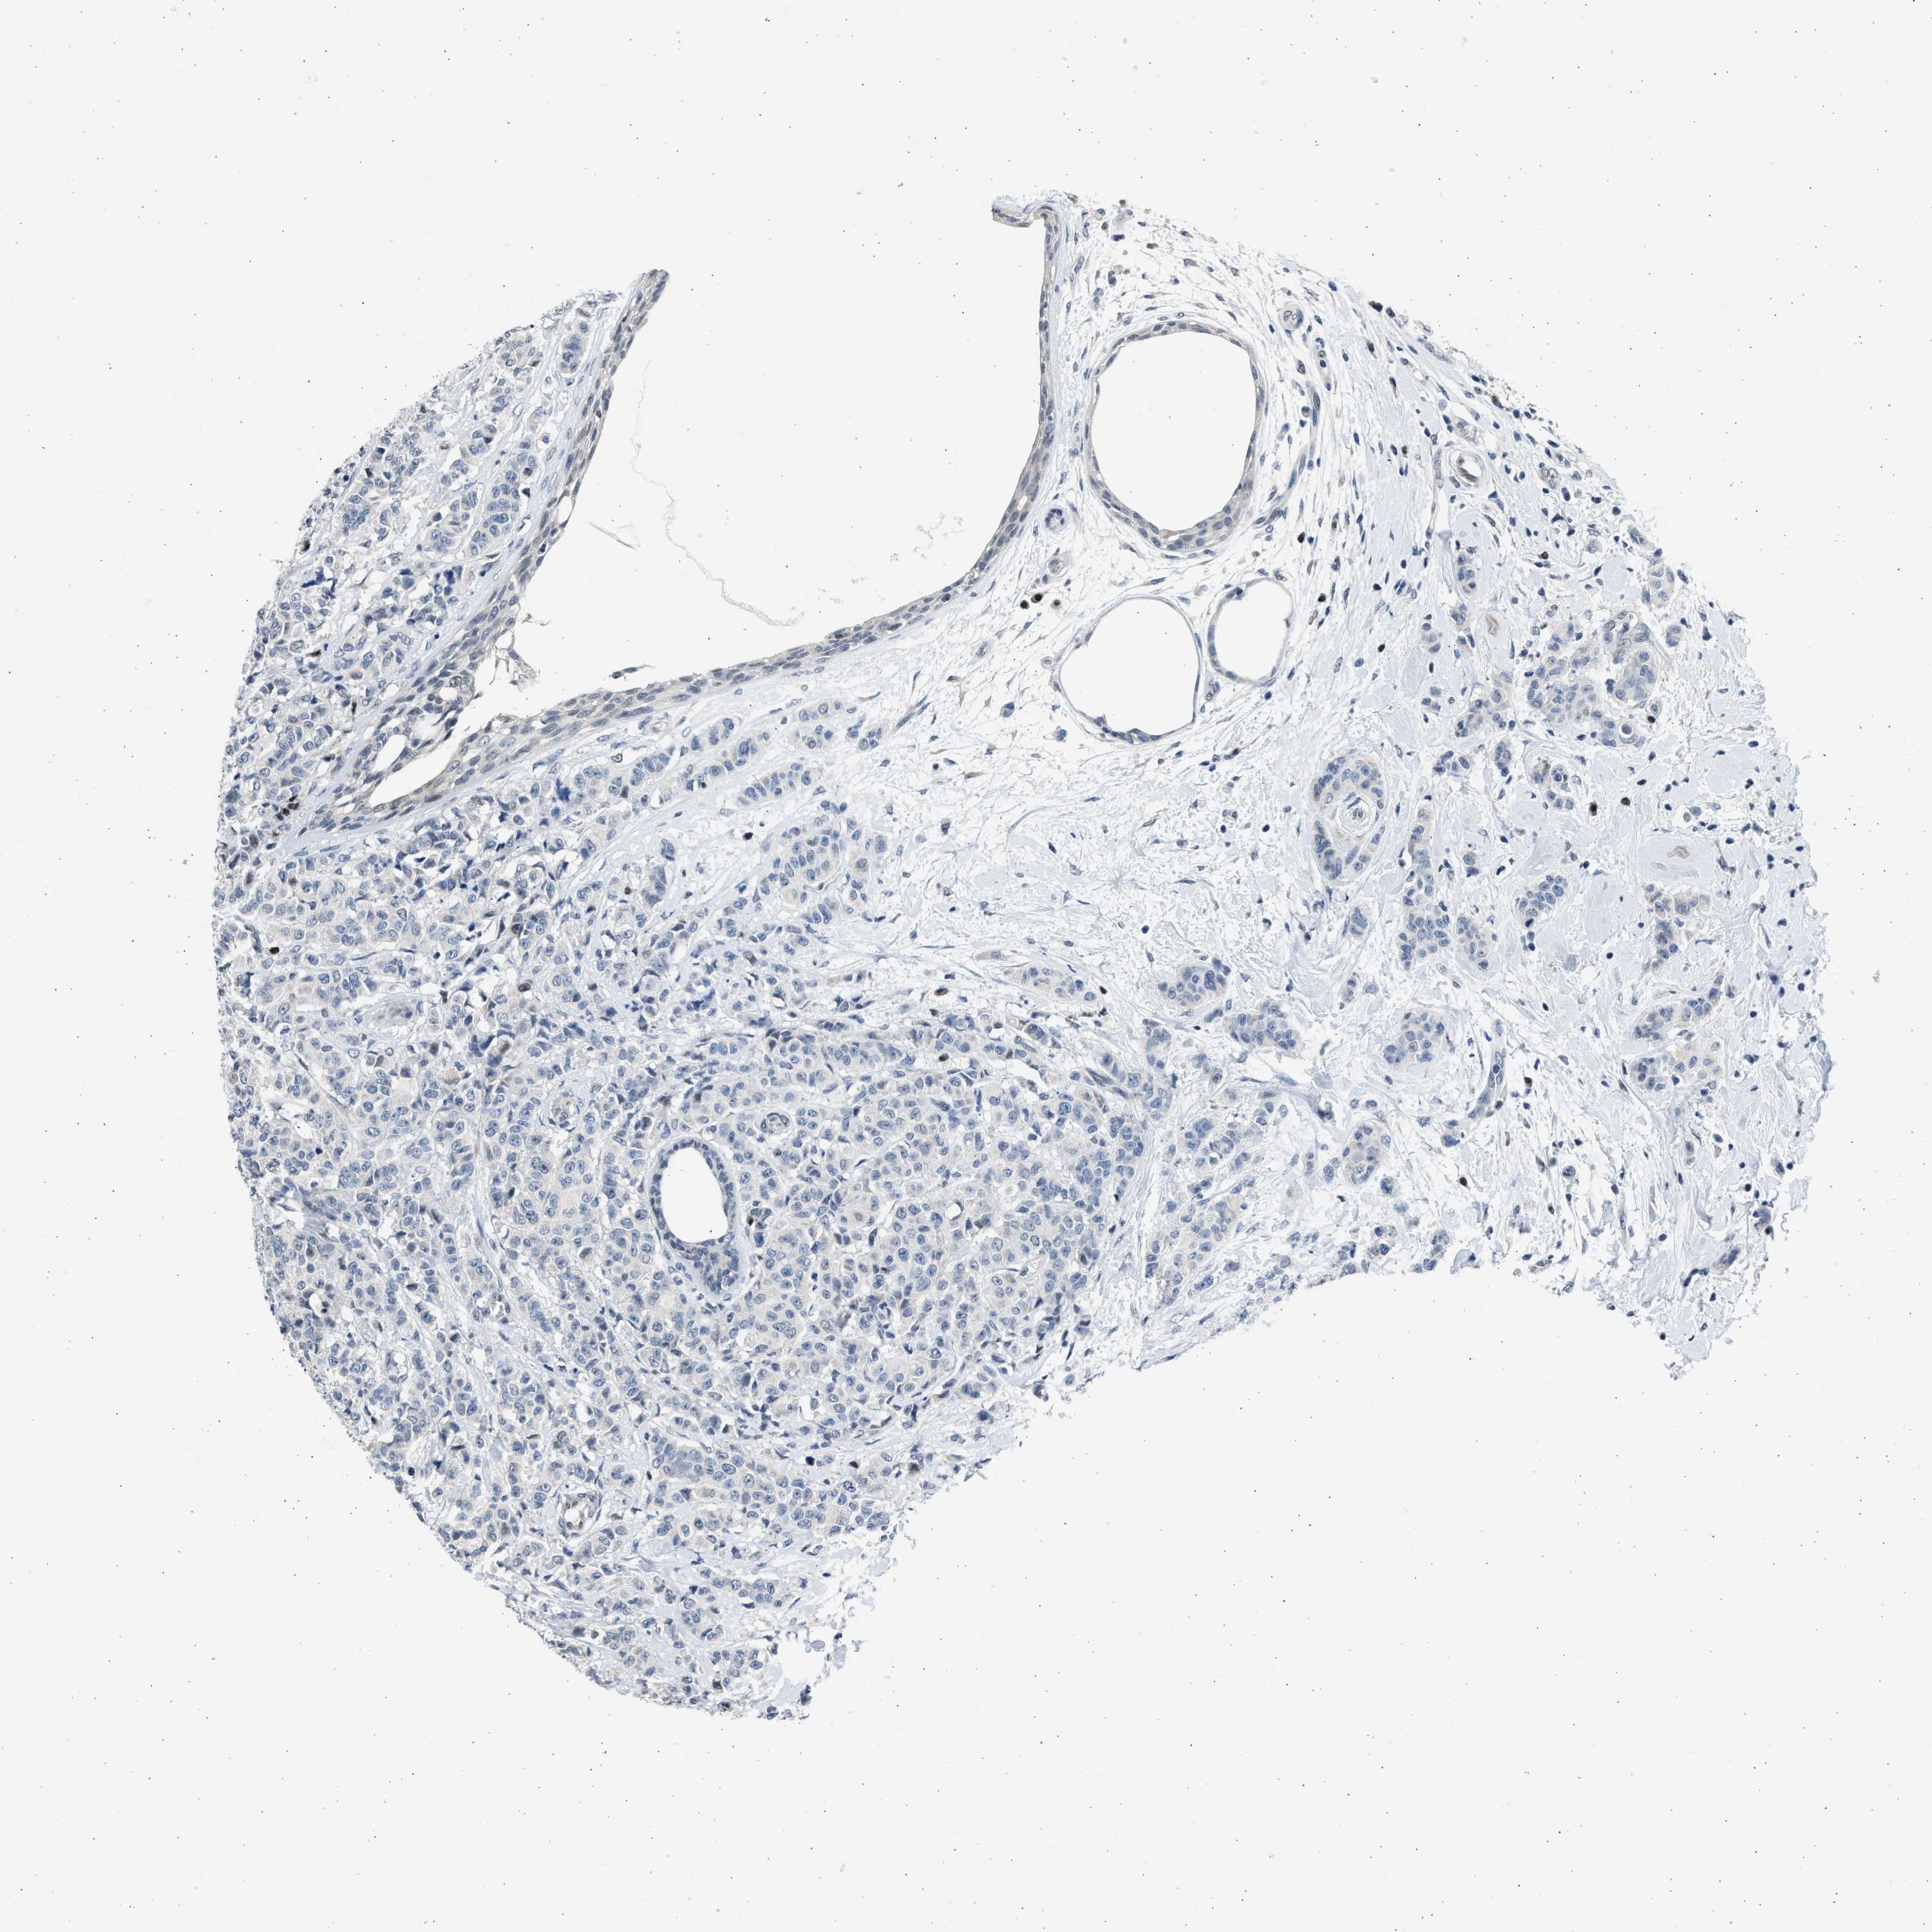

CANCER BREAST CANCER Show tissue menu

BRCA TCGA BRCA VALIDATION PROTEIN EXPRESSION

ANTIBODIES

AND

VALIDATION